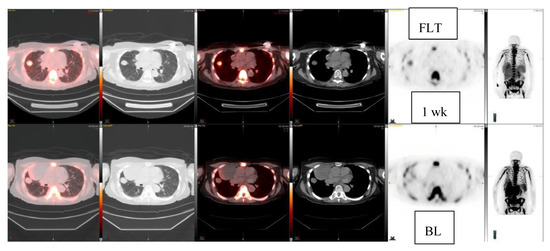

| 74/F | Fibrous tumor, pleura Lung mass | 3.0 2.4 × 1.9 | 1.7 2.5 × 2.0 1 week | Fibrous tumor 3.0→1.7 No FDG response | −43% |